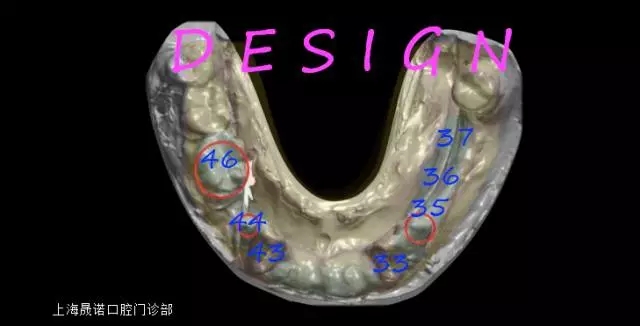

種植位點設(shè)計

分別設(shè)計位點于右下3,4,6,左下3,5,6,7。綜合考慮后,為獲得更優(yōu)的導(dǎo)板固位,決定保留雙側(cè)尖牙支持導(dǎo)板,導(dǎo)航下植入右下4,6;左下5,6,7;摘除導(dǎo)板后,雙側(cè)尖牙進行即拔即種。